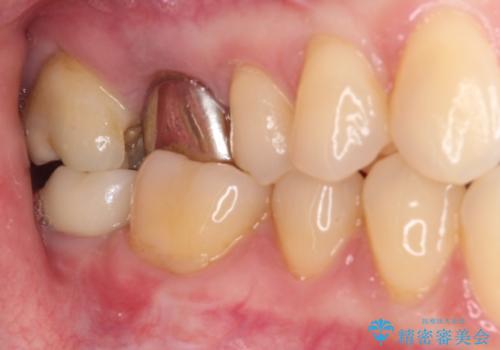

ゴールドインレーは銀歯のインレーやセラミックインレーと比べ、「技工操作の精度が高く、適合が著しく良い」というメリットがあります。特に上の奥歯は歯科医師の操作が行いにくいため、「適合の良さ」は再治療のリスクを防ぐ上でとても重要な要素となります。

上の奥歯は金属色が見えることもないため、審美的な問題は全くありません。

咬み心地はとても良好で、全く違和感がなく、患者様には大変満足していただきました。